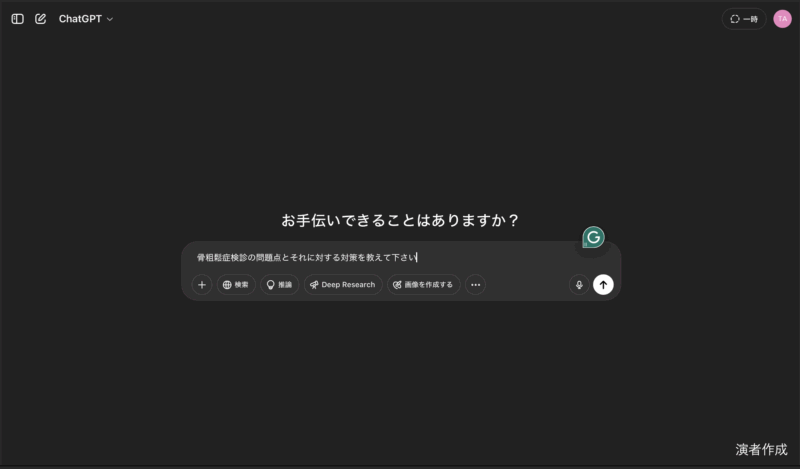

20時過ぎから, 私がclosing remarksとして, 10分で骨粗鬆症検診の問題点とその対策, および各県庁所在地での現状について, チャットGPTからの回答をからめてお話ししました. 途中で, 自分の大腿骨頚部骨折のことも取り上げました.